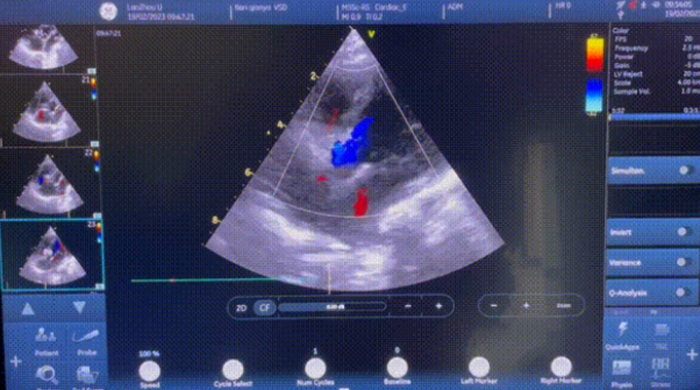

2月19日,兰大一院院心脏中心成功应用MemoSorb全降解封堵器为一例室间隔缺损并膜部瘤患者行经导管室间隔缺损封堵术,成功完成甘肃地区首例植入。

患者术前经全面检查,诊断为室间隔缺损并膜部瘤。综合患者及家属意见,兰大一院心脏中心手术团队讨论后,拟使用我国自主研发的MemoSorb全降解封堵器系统行室间隔缺损封堵术。术中在造影指导下顺利将导引导丝送至心室腔内,成功建立手术入路,再送入输送鞘管到右心室。随后,沿鞘管将一枚MemoSorb全降解封堵器输送到位后,牵拉成型线、锁定封堵器,使得其完全成形。影像显示,MemoSorb全降解封堵器形态良好、封堵完全、无残留分流后,释放封堵器、回收成型线,顺利完成手术。